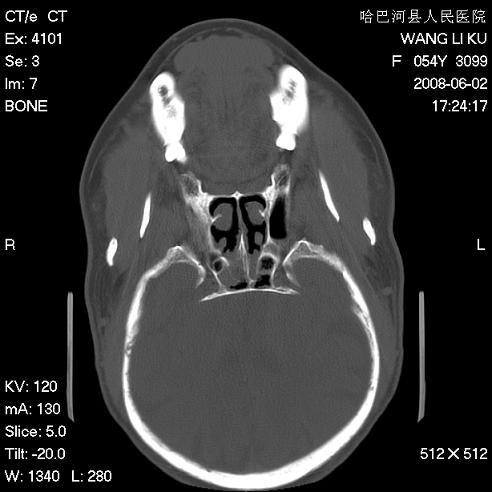

标题: CT13803:反复性鼻塞、流涕一年余 [打印本页]

标题: CT13803:反复性鼻塞、流涕一年余

1.全组副鼻窦炎2.双侧上颌窦积液

全组副鼻窦炎

.全组副鼻窦炎2.双侧上颌窦积液

1)全副鼻窦炎(左侧上颌窦黏膜下囊肿或息肉)。2)左眼眶肌锥内不规则小结节状软组织密度影;考虑为小血管瘤可能。建议行ct增强扫描检查。

全组副鼻窦炎,左侧肌锥内不规则形软组织肿块影,与眼外肌密度相当,左侧视神经受压,肿块与视神经及眼外肌分界清晰,眼外肌无增粗,眶壁无破坏,球后脂肪间隙不模糊,考虑良性改变,小血管瘤或神经源性肿瘤可能,建议增强扫描。

谢谢,增强扫描做了,眶内病灶与海绵窦同步明显强化,血管瘤